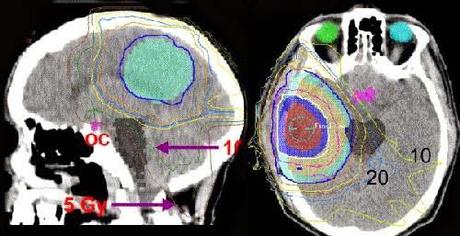

La Planificación:

Este es un proceso personalizado de diseño de su tratamiento. Aquí el radioncólogo procederá a contornear en un planificador (ordenador específico para diseñar los haces de tratamiento y hacer los pertinentes cálculos de dosis de radiación) tanto los llamados órganos críticos (órganos sanos que nos interesa reciban no más de una determinada dosis para no dañarlos: tronco cerebral, cerebro sano, oído medio, cristalinos, nervios ópticos, etc) como los tejidos u órganos diana de cada caso (donde si nos interesa que se reciba una dosis tumoricida según cada caso: el tumor). A partir de aquí los encargados de hacer la mejor planificación posible serán los técnicos dosimetristas y los radiofísicos. Ellos deberán velar por que nuestra prescripción de dosis se ajuste de la mejor manera posible. Luego el radioncólogo debe supervisar junto con el radiofísico de que todo esté en orden y dará su visto bueno, o no, al tratamiento. Una vez acordado el plan, se validará y ya estará listo para comenzar el tratamiento.